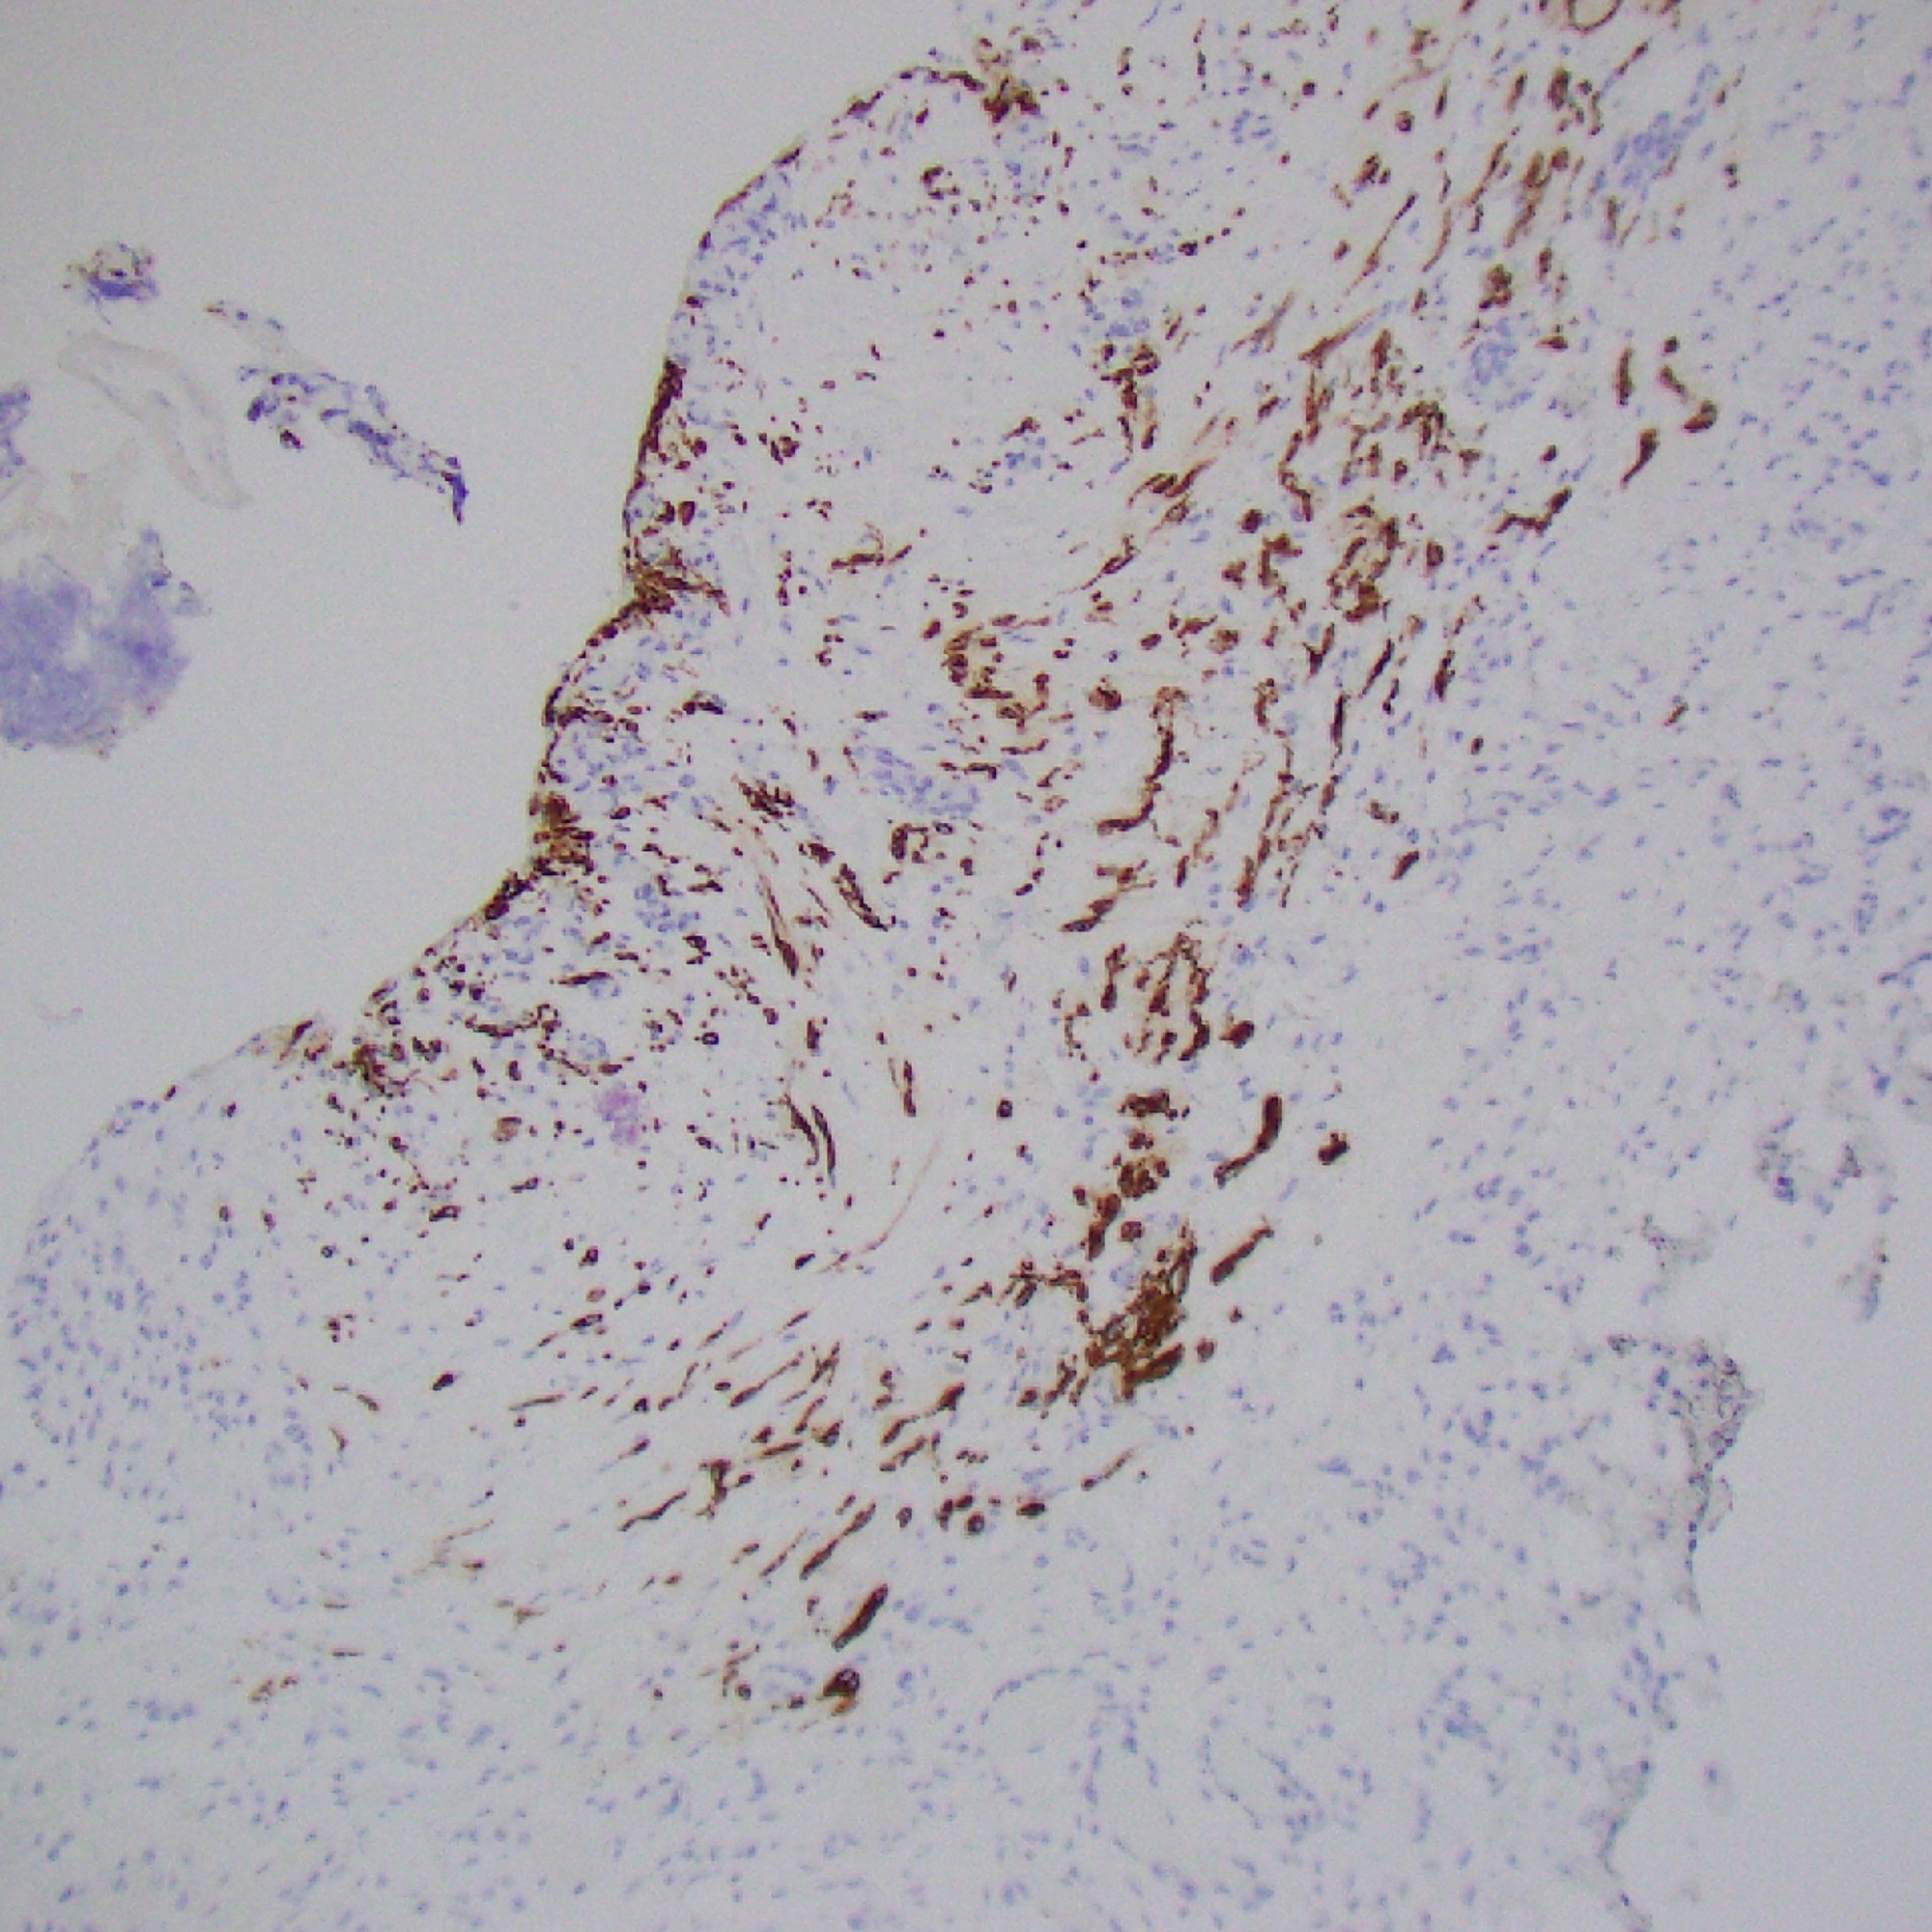

Case 7

Images

Pouch of skin internally lined by arachnoid tissue (EMA pos) and glial tissue (GFAP pos)

Diagnosis

Myelomeningocele

- A neural tube defect characterized by a cleft in the vertebral column